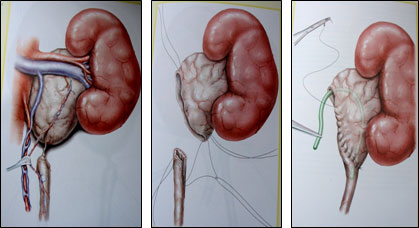

1. Amikor a kezelési művelet választott hydronephrosis (az arany standard) marad műanyag prilohanochnogo uréter által Hines-Andersen (ábra6).

Ábra 6 Kezelés Hines-Andersen.

A. meghatározása uréter szűkület. B. stenosis kimetszés, eltávolítását a vesemedence, húgyvezeték boncolás vdol.V. Formation lohanochnomochetochnikovogo anastomosis.